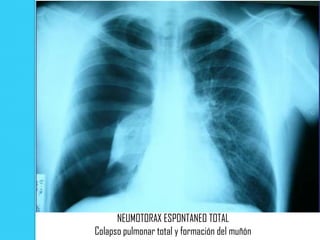

NEUMOTORAX ESPONTANEO TOTAL

Colapso pulmonar total y formación del muñón

Signos radiológicos  Colapso pulmonar de mayor o menor un grado dependiente de la magnitud del neumotórax. Se considera total cuando hay un colapso pulmonar máximo. El grado de colapso es mínimo, cuando el espacio que hay entre la pleura visceral y parietal es menor de 1 cm.  La denominada " linea pleural " que es la pleura visceral del pulmón colapsado  3) Ausencia de trama vascular pulmonar distal. Suele ser de localización apical debido a la tendencia del aire a ascender.

NEUMOTORAX ESPONTANEO TOTAL Colapsopulmonar total y formación del muñón